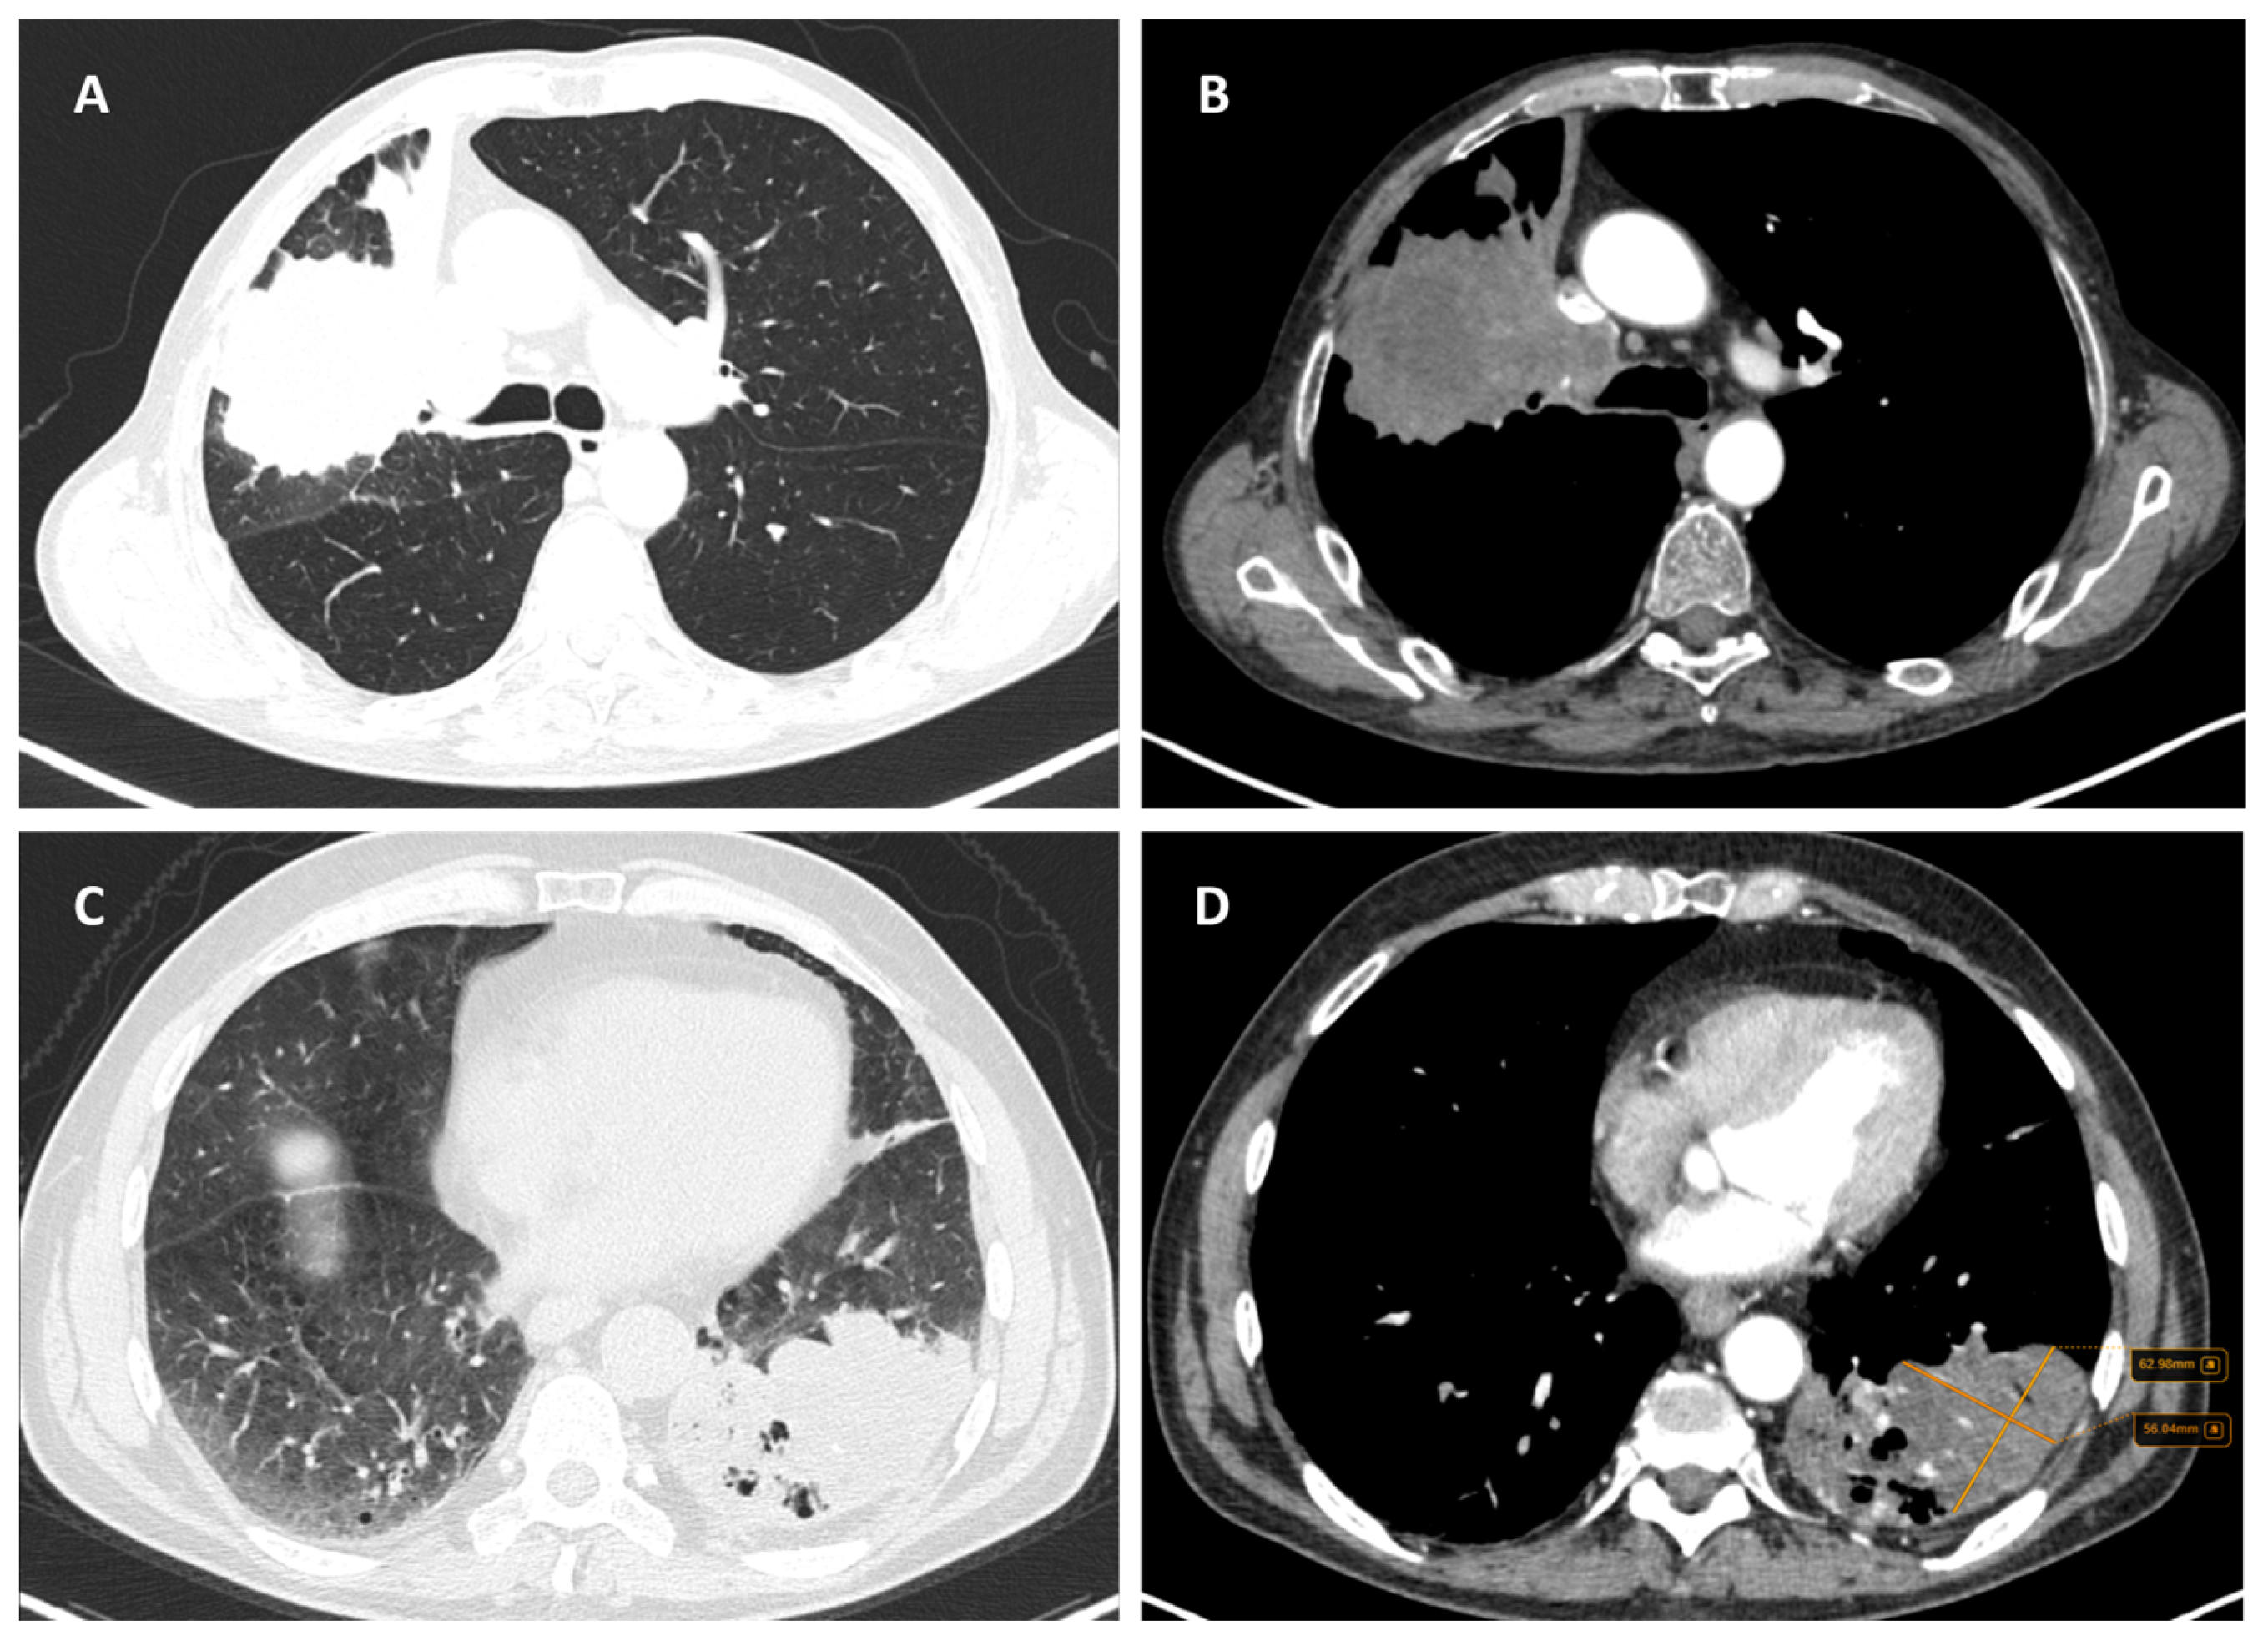

Considering the exclusion criteria previously mentioned, a total of 58 patients were analysed in this study, in which 26 cases were pathologically proven to be adenocarcinoma (Figure 1), 22 cases were shown to be squamous cell carcinoma (Figure 2), and 10 cases were shown to be small cell lung cancer (Figure 3).

Figure 1.

Axial CT of two different cases of adenocarcinoma: (A) a right peripheral mass (the maximal tumoral diameter over three centimetres) with spiculated margins, a small atelectatic area and hilar invasion is highlighted on lung window; (B) soft-tissue window that shows the same tumour as (A) with central necrosis and pleural invasion, including the main right bronchus; and (C,D) a peripheral mass with adjacent pneumonitis in the left lower lobe.